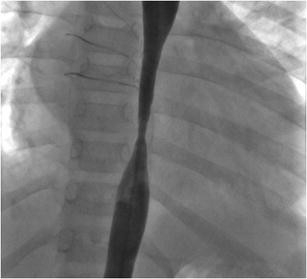

Fig. 1